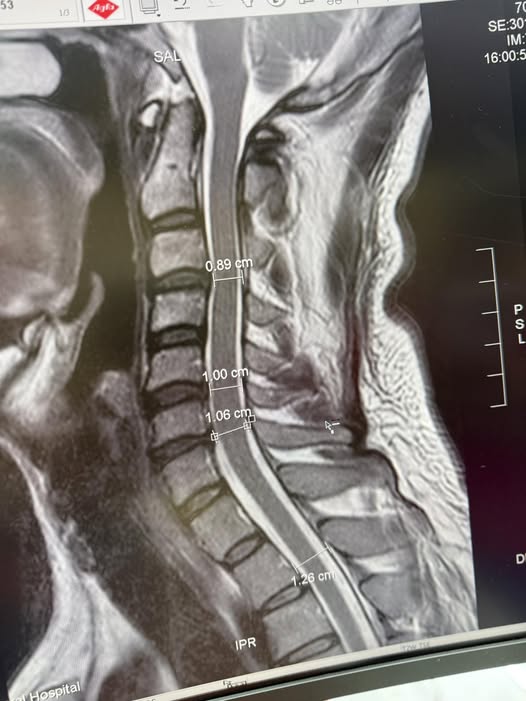

Cervical Spine Treatment Cases 頸椎治療案例 標題:當香港跟倫敦所有名醫都說頸椎必須開大刀:一位香港母親,如何在台北三週內逆轉... 2026.03.18 「徐國峰醫師的診間針刀筆記」 影像上的「死刑」,針尖下的「新生」:一個跨越 2500 ... 2026.03.03 飛鷹歸來:解開 9G 鎖喉的「脊椎減壓」奇蹟 —— F-16 飛官龔先生頸椎減壓針刀復原長... 2026.01.15 醫案深探:當頸椎失去靈魂的曲線,神經根在狹縫中求生。 深夜的痛覺,為什麼你的頸椎... 2026.01.11 「不是花粉!不是塵蟎!長年過敏性鼻炎的真正原因,可能藏在你的頸椎深層筋膜裡」 文... 2025.12.08 🌟新竹范小姐的頸椎奇蹟醫案分享 ——手術與非手術之間,她找到屬於自己的第三條路 ✅... 2025.12.03 脊椎噩夢兩年三開!花費新台幣三百萬元 頸椎手術黑洞蒸發公務員積蓄:300萬,換不回... 2025.11.21 ⭕️低頭的代價:智慧手機正在悄悄「鎖死」台灣八百萬長輩們的殘破頸椎 🛑頸椎人工椎間... 2025.11.06 跨越半個地球的希望:華僑黃阿姨的頸椎奇蹟。 美國頸椎手術ACDF要價台幣150-250萬。 ... 2025.10.03 【200公斤水泥的血淚啟示:揭開你頸椎上「慢性重量」的驚人真相與致命代價! 【⚠️ 醫... 2025.09.29 ❇️頸椎推拿的風險警鐘:從一個真實案例談起 ‼️電流竄過手臂的那一瞬間,他的人生被改... 【醫療案例探討真相|PRP打進頸椎椎間盤?一名患者一年的手腳無力,背後的風險不可不... 2025.08.16 🚨 MRI 一張 → 馬上開刀?自費五十多萬更換兩節人工椎?廚師的抉擇 (文:徐國峰醫師... 2025.08.13 【當針刀無法再沉默——一位針刀醫師關於「非手術底線」的誠實告白】 【不是每一個人... 一張86萬的頸椎手術帳單,讓我們重新認識什麼叫做「選擇」。 「問題關鍵不是價格,而... 1 2 3 4 5 下一頁 →